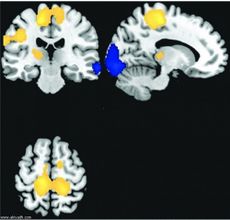

متلازمة كلاينه-لفين Kleine–Levin syndrome (KLS)، وتعرف أيضاً بمتلازمة الجمال النائم Sleeping Beauty syndrome، أو متلازمة فرط النعاس الدوري، هو اضطراب نوم نادر يتميز بفرط النوم العرض المتواصل وتغيرات معرفية أو مزاجية. كما يعاني الكثير من المرضى من النهام، فرط النشاط الجنسي وأعراض أخرى. بشكل عام يعاني مرضى متلازمة كلاينه-لفين من نوبات متكررة من المرض عادة ما تستمر لمدة لا تقل عن أسبوع، وفي بعض الأحيان تستمر أشهر. تؤثر هذه الحالة بشكل كبير على الحياة الشخضية، المهنية والاجتماعية للمصابين. حدة الأعراض ودورة المتلازمة تختلف من مريض لآخر. معظم الحالات تصاب بحوالي 20 نوبة على مدار عشر سنوات تقريباً. وقد تطول الفترة بين النوبة والأخرى لعدة شهور. عادة ما تكون بداية الحالة في أعقاب عدوى ڤيروسية؛ تم رصد عدة ڤيروسات مختلفة تؤدي إلى بدء الاصابة بمتلازمة كلاينه-لفين. عادة ما يتم تشخيص الحالة بعد استثناء الأمراض المشابهة؛ فحوصات التصوير بالرنين المغناطيسي، التصوير الطبقي المحوسب، البذل القطني، واختبار السموم تستخدم للوصول للأمراض الأخرى المحتملة. آلية المتلازمة غير معروفة، لكن يعتقد أن المهاد قد يلعب دوراً محتملاً في الإصابة بها. أوضحت SPECT وجود نقص في إمدادات الدم للمهاد لدى المصابين أثناء النوبة.

هذا الاضطراب غير معروف السبب حتى الآن. حيث تكون الأشعة المقطعية والرنين المغناطيسي للدماغ والاختبارات العصبية الأخرى طبيعية. وحديثا، أظهرت بعض التقارير نقصاً في انسياب الدم في المنطقة المهادية وتحت المهادية والجبهية من الدماغ باستخدام الأشعة المقطعية الفوتونية خلال نوبة المرض. وأظهرت دراسة أخرى حديثة نشرت عام 2014 تغيرات في عمليات الأيض في مناطق عدة من الدماغ. ويعتقد أن هذا المرض مرتبط بتغيرات في بعض الجينات ولكن الأبحاث لم تظهر نتائج واضحة بعد بسبب ندرة المرض.